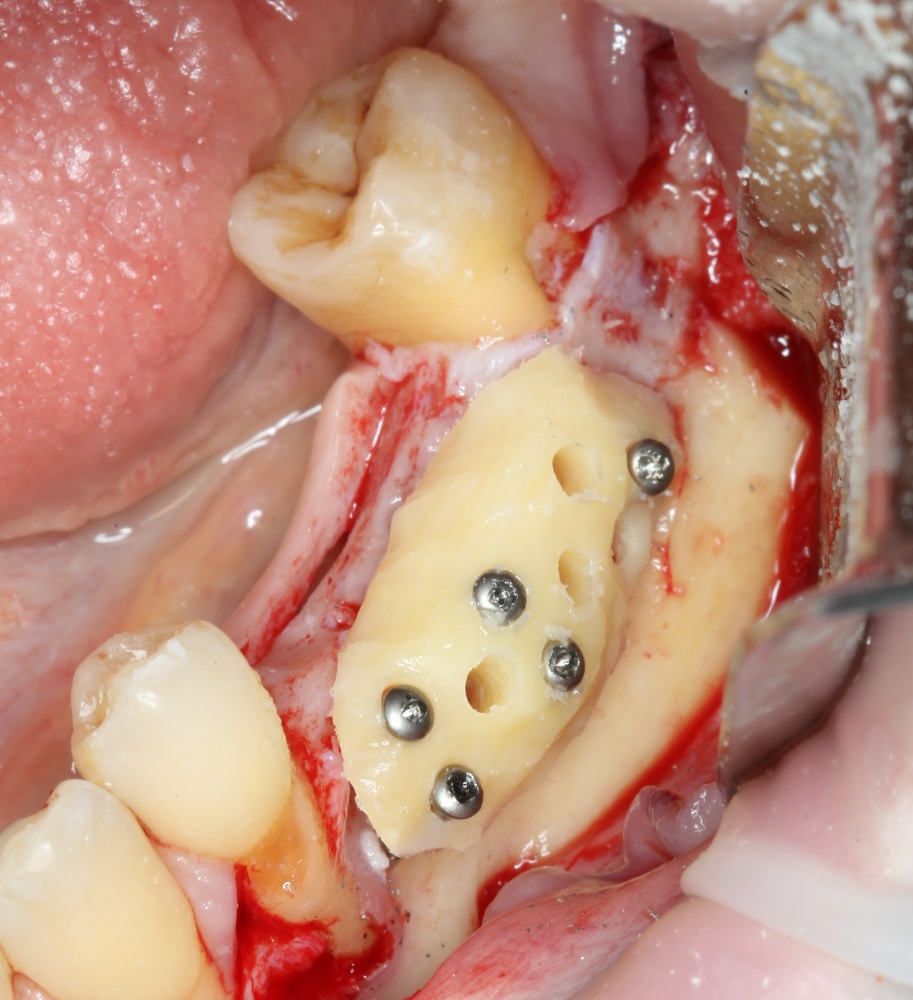

Готовим его к фиксации:

A09A5451 (2)

Многие ошибочно предполагают, что большое количество дырок в блоке нужно для того, чтобы «всё лучше срослось». На деле, большое количество отверстий в аутокостном фрагменте даст нам возможность переставлять вины и адаптировать его «на месте». А это особенно важно для одномоментной установки имплантов, потому что винты не должны попасть в проекцию будущей лунки.

Фиксация костного блока:

A09A5452 (2) A09A5453 (2)

Для этого стоит использовать длинные винты. В противном случае, при подготовке лунки под имплантат костный блок может отлететь.

Переставляя винты и пришлифовывая аутокостный фрагмент, можно добиться более-менее точного соответствия принимающему ложу:

A09A5457 (2) A09A5458 (2)

Теперь можно готовить лунки под импланты:

A09A5459 (2)

В данном случае я планирую установить импланты Nobel Replace Conical Connection:

A09A5461 (2) A09A5462 (2)

Операция почти закончена. Обратите внимание, на два момента:

1. Блок явно больше, чем нужно. Это связано с тем, что в процессе интеграции происходит атрофия графтов (причем, абсолютно любых), и мы должны закладывать этот уровень атрофии при планировании объемов костной пластики. В среднем, плюс 30% к тому, что нам нужно.

2. Между блоком и принимающим ложем есть пустое пространство. Поэтому область операции необходимо изолировать барьерной мембраной от быстро растущих мягких тканей. Я использую Geistlich BioGide 25×25 mm: